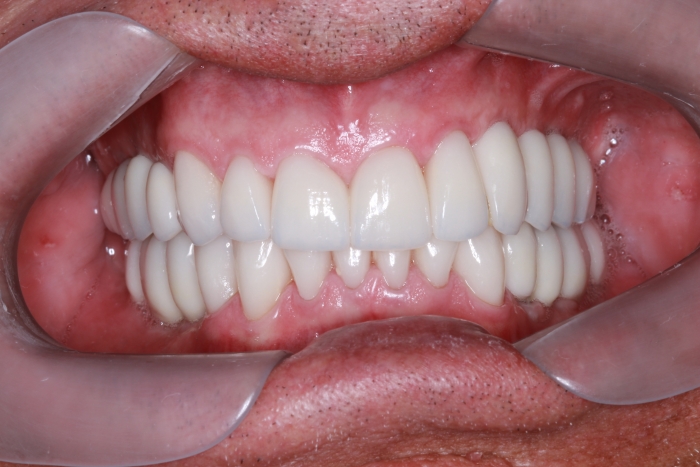

Facetas e dentes em porcelana sobre implantes